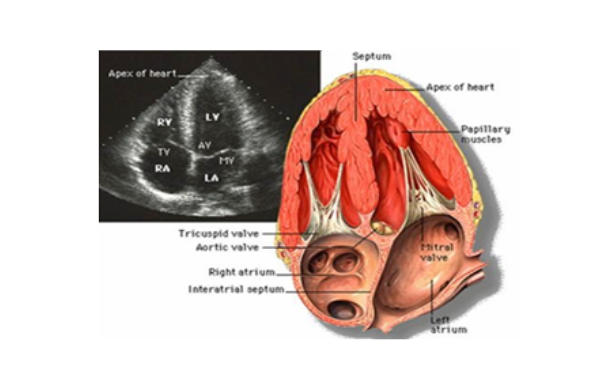

Hình ảnh siêu âm tim 2D thu được khi chùm tia siêu âm đi qua 1 mặt cắt của tim, qua đó đánh giá được vị trí và tư thế của tim, kích thước của các buồng tim, độ dày và vận động của các thành tim, chức năng giãn và co bóp của cơ tim, các gốc mạch lớn, hình thái và vận động của các van tim, các lỗ khuyết của các vách ngăn trong tim, u hoặc huyết khối trong tim, dịch màng ngoài tim. Các mặt cắt thường được sử dụng trong siêu âm tim 2D gồm: mặt cắt trục dọc cạnh ức trái, các mặt cắt trục ngang cạnh ức trái, các mặt cắt từ mỏm tim, mặt cắt trên hõm ức, mặt cắt dưới bờ sườn.

Siêu âm tim kiểu 2D, mặt cắt 4 buồng từ mỏm tim, thấy nhĩ trái (LA), thất trái (LV), nhĩ phải (RA), thất phải (RV), van 2 lá (MV), van 3 lá (TV), van động mạch chủ (AV). Ngoài ra còn thấy vách liên nhĩ và vách liên thất.